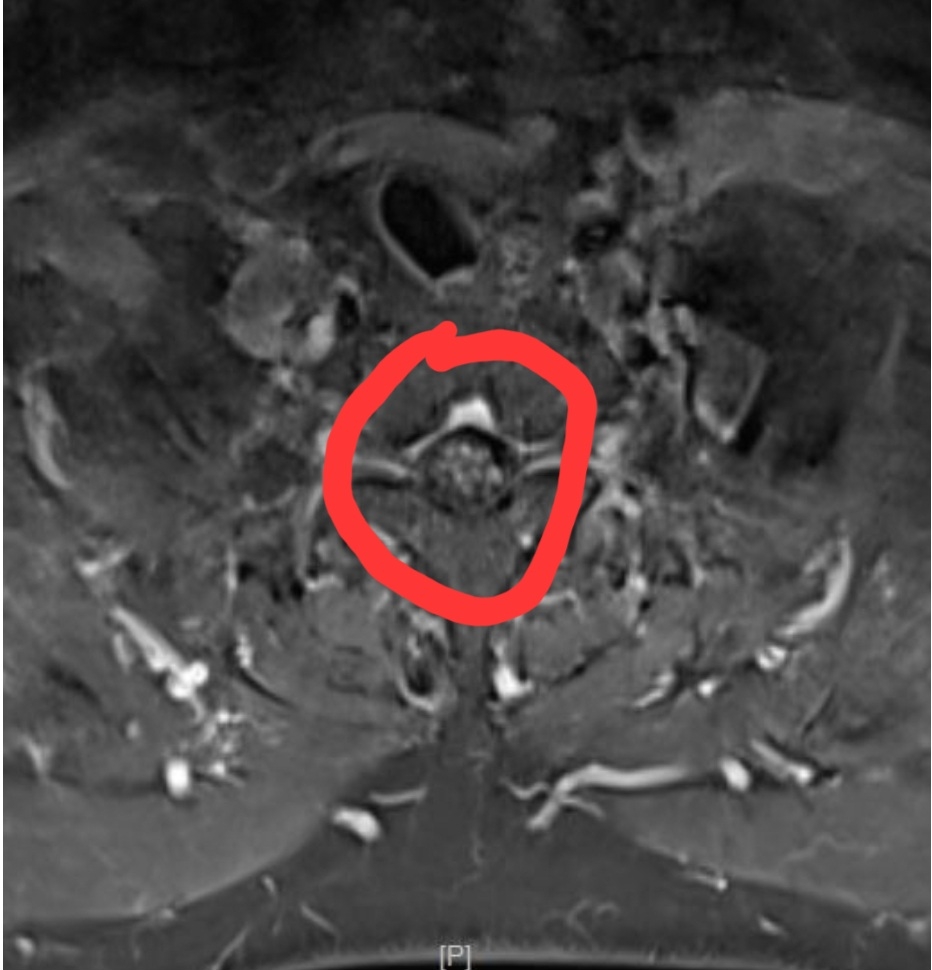

入院核磁共振检查提示T1海绵状血管瘤

术后复查提示海绵状血管瘤全切